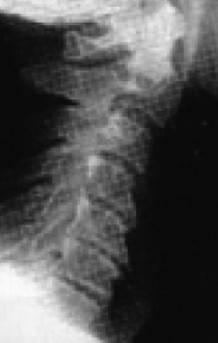

Иллюстрация к книге — Биогимнастика для лица: система фейсмионика [i_014.jpg]

Рис. 10а. Череп старого человека

А поскольку нижняя челюсть является основной костью лицевой части лица, любые ее изменения влияют на общий вид лица.

Внешне это проявляется в том, что его нижняя часть приобретает более вялые очертания, мягкие ткани провисают, овал теряет свою четкость, снижается тонус кожи щек, подбородка и шеи, в результате чего очертания лица приобретают характерный возрастной вид. Далее Г. Лэнгстайн добавил: «Хотя врачи всегда знали, что кости со временем меняются, но как это проявляется с возрастом – не смогли оценить до конца».